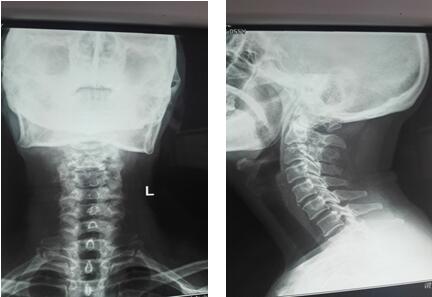

术前颈椎正侧位X线片